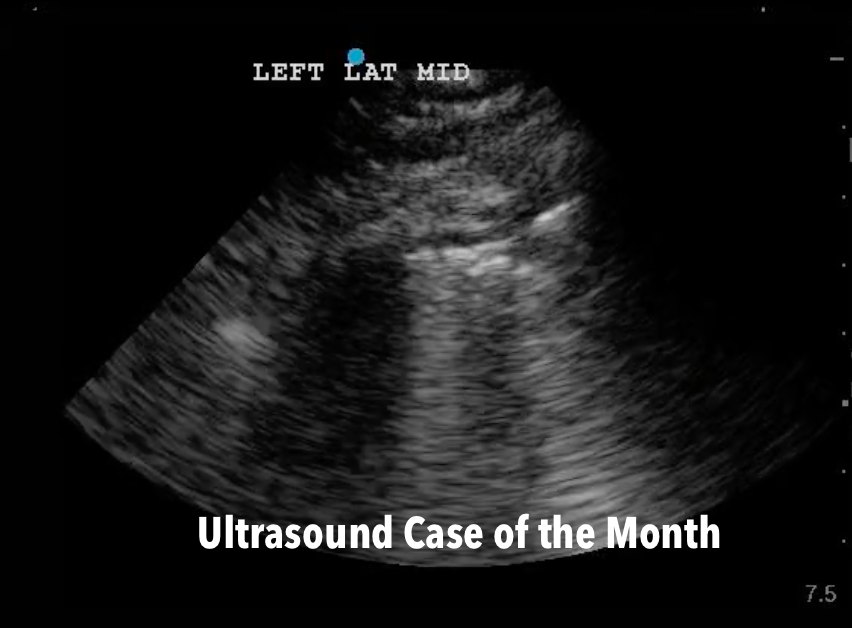

/During Grand Rounds this week, we had the pleasure of hosting our Brian Gibler visiting lecturer Dr. John Deleda who Spoke about Henry Ford Hospitals COVID-19 response and the leadership lessons he learned over his career. Dr. Della Porta then gave us the rundown on different blood products and using TEG. We discussed PPROM, Breech delivery, and neonatal resuscitation with Dr. Crawford. The CPC showdown with Dr. Minges and Dr. Brower ended as a case of Hyperleukocystosis and Leukostasis. We ended the day with a talk from our PEM colleagues on inborn errors of metabolism.